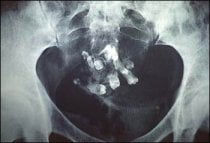

Resimde içinde diş içeren bir dermoid kistin

röntgen filmindeki görüntüsü izlenmektedir.